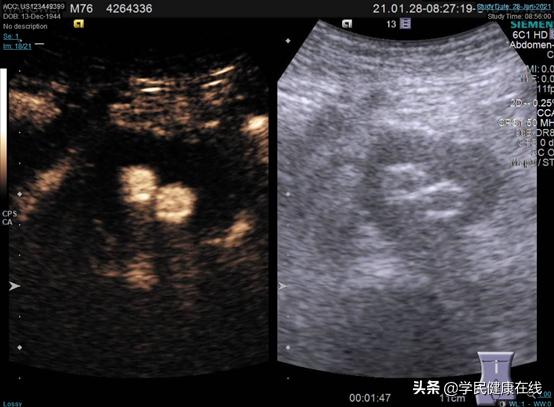

2021年1月22日,在手麻科和泌尿外科叶雄俊、刘军医生的帮助下,我们两个科室合作完成了全国首例腹腔镜下EVAR术后II型内漏的处理,术中根据术前的影像分析,很快定位到肠系膜下动脉和两对腰动脉,一根骶正中动脉,分别夹闭切断。术前充分的准备,术中没有意外发生,手术顺利完成。术后复查超声造影,证实已无造影剂漏入瘤囊。

图5. 术前超声造影,可见后壁有造影剂进入

图6. 术后造影,已无明显造影剂进入瘤囊